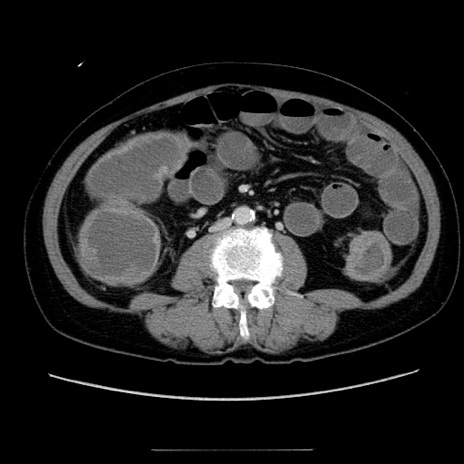

症例5(横断像)

【症例】70歳代女性

【主訴】お腹が張る

【現病歴】1週間くらい前から腹部膨満の自覚あり。昨日夜から増悪したため、本日救急外来受診。

【身体所見】意識清明、BT 36.5℃、BP 165/106mmHg、HR 80bpm、SpO2 98%、腹部:膨満、軟、自発痛・圧痛なし、触診にて不快感あり、腸蠕動音:減弱

【データ】WBC 12600、CRP 1.04